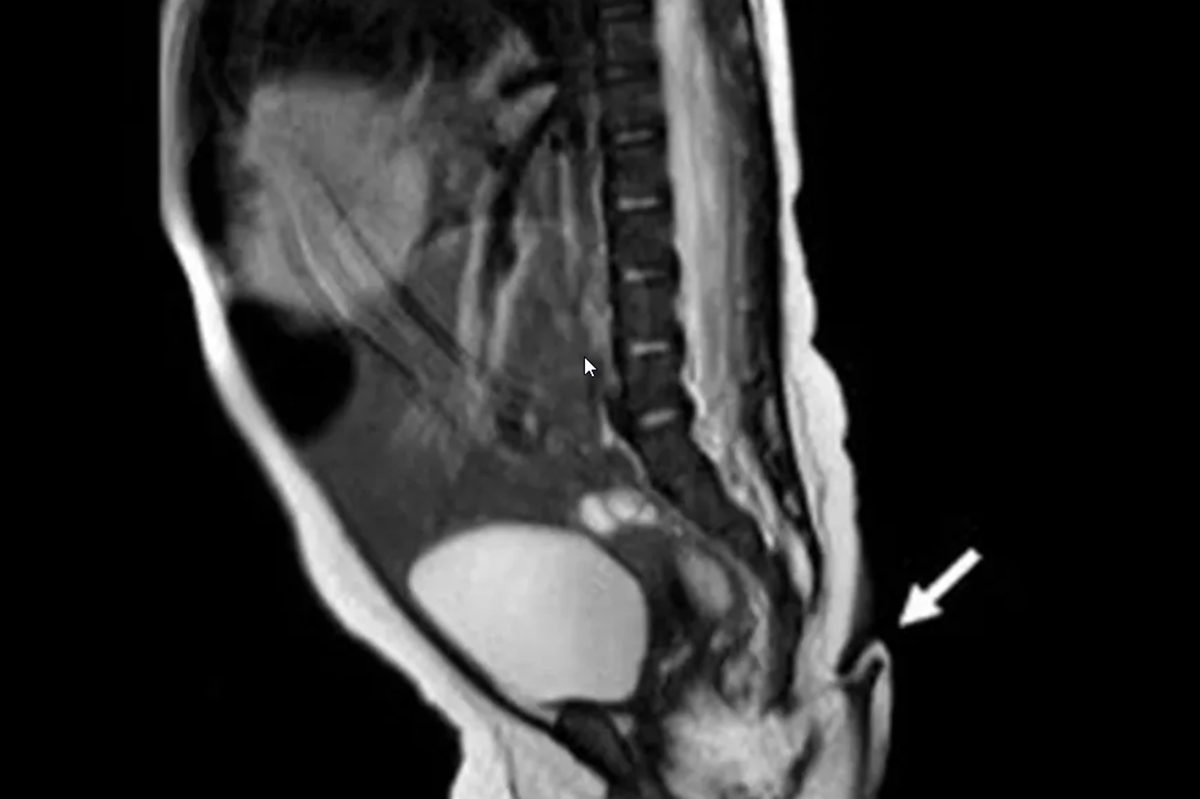

Los médicos, dirigidos por el Dr. Josué Rueda, detallaron el incidente en la publicación. De acuerdo con su reporte, el embarazo no tuvo complicaciones, pero cuando revisaron al recién nacido vieron que la extremidad sobresalía al final de su coxis. Al parecer, podía moverse sin causarle dolor a la bebé, pero no tenía ninguna clase de movimiento espontáneo. Durante las pruebas, la niña lloró al ser pinchada con una aguja, lo que probaba que había conexiones nerviosas.

La extremidad solo fue visible fuera del vientre de su madre. Tenía una longitud de 5,7 centímetros, con entre 3 y 5 milímetros de diámetro y se encontraba en la hendidura interglútea.

El artículo refirió que el nacimiento de la pequeña había ocurrido con normalidad. Fue una cesárea en un hospital rural. Además, durante el embarazo no hubo ningún registro de exposición a radiación o teratógenos, que son los agentes capaces de los defectos congénitos.